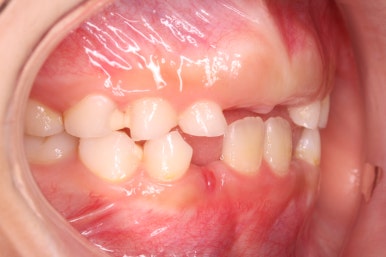

7개월 뒤 사진입니다.

해당 부위 어금니가 약간 나왔씁니다. 가장 간단하게 치료를 할 수 있는 상황이 되었네요.

매우 운이 좋았던 경우입니다.

장치를 부착했습니다.

할터만 장치(Halterman)는 굉장히 간단한 컨셉의 장치인데 매우 효율적입니다.

앞쪽 치아에서 반지처럼 둘러싸고 이를 이용해 어금니를 뒤로 쭈욱 당겨주면 끝.